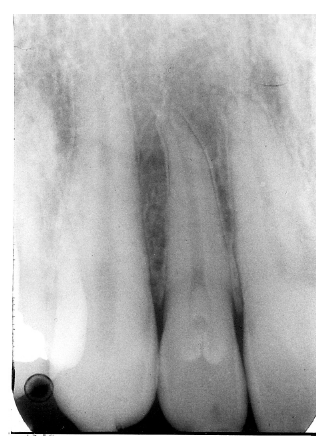

Figure 13 illustrates apical periodontal pathosis in the area of the right central incisor. Note the loss of continuity of the lamina dura and the widened periodontal ligament space on the affected side.

Figure 13 - Apical Periodontal Pathosis

Figure 13